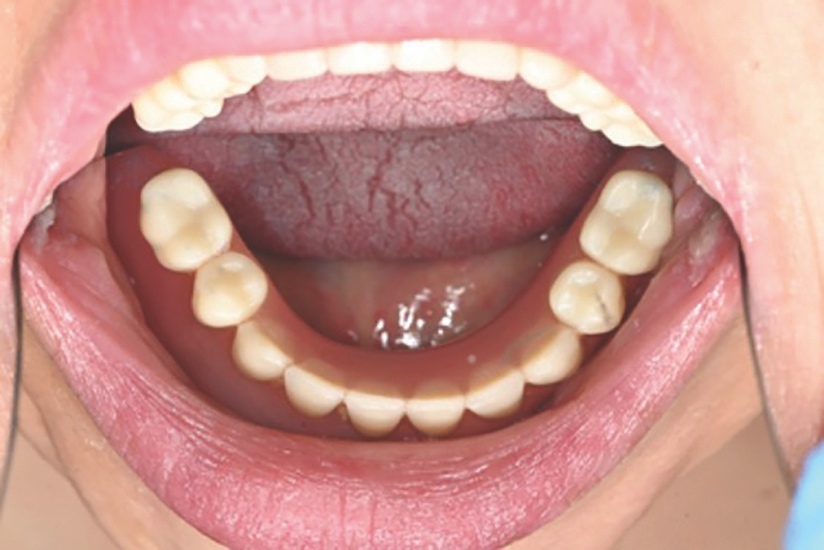

Upon clinical examination, she presented with a Class III skeletal pattern (Figure 1) with average vertical proportions, a hypoplastic maxilla, and she was edentate. She had undergone multiple previous attempts at denture construction; however, these were of limited success.

Intra-orally, the patient presented with an atrophic mandible and maxilla (Cawood and Howell13 Class VI and V, respectively) and was edentate (Figures 2 and 3). An orthopantomogram (Figure 4) confirmed the clinical findings and also demonstrated the proximity of the reduced maxillary ridge height to the maxillary sinuses.